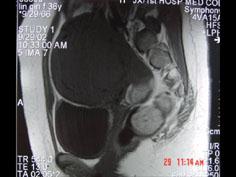

问题 女性,36岁,腹痛,自觉摸到包块,行B超检查提示盆腔内巨大包块,进一步行MRI检查,如图所示,考虑为 ( )

选项 A、卵巢囊肿 B、膀胱憩室 C、子宫腺肌瘤 D、子宫癌 E、子宫肌瘤

答案 C